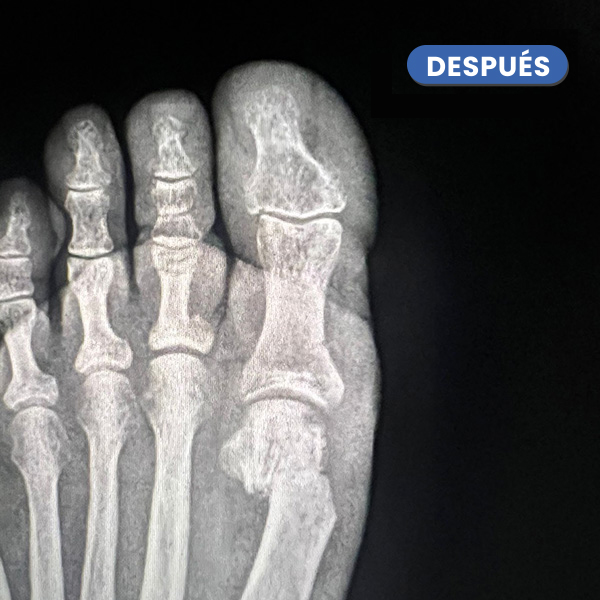

En la imagen cabe destacar la desaparición del juanete y del heloma o cayo sobre el cuarto dedo.

La corrección del Juanete nos permite modificar la desestructuración de los dedos menores segundo y tercero que este caso está en ráfaga y este último sobre el dedo vecino, cuarto dedo.